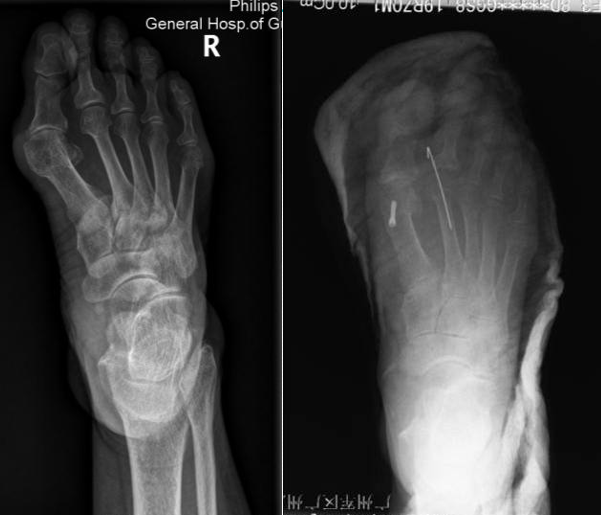

典型病例例1:姚X,女,78Y。

Chevron+第二跖骨Weil

例2:芦XX,男,21Y。

例3:朱XX,男,23Y。

例4:罗XX,女,60Y。

左足:第1-5跖趾关节脱位,足拇外翻。

胼胝体:第一跖骨内侧,第2/3跖骨头跖侧,第5跖骨头跖/外侧。

左足:第2-5趾爪形趾。

右足:第4趾爪形趾,趾间关节胼胝,疼痛。

右足:第5跖骨头跖/外侧胼胝。

CT重建:第1跖骨头破坏。

术式:左足:第1跖趾关节融合+第2-5跖趾关节成形术;右足:第4趾间关节融合+第5跖趾关节成形术